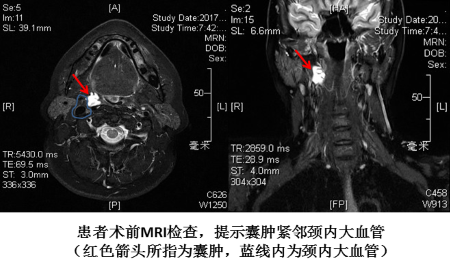

“只有手术完整切除囊肿及瘘管,患者的疾病才能得以痊愈,所以以往治疗过的医院多次的切开排脓并不能解决患者的痛苦。”叶京英说。但问题来了,患者脓腔大,与咽侧壁、颈内大血管关系密切,又曾反复感染,手术难度很大,口内入路切除容易切除不干净,并可能伤到血管、引发大出血,颈外入路创伤大,且感染的囊肿位置高,不易切除,有可能需要行下颌骨裂开术才能到达病变部位,术后有发生咽瘘的可能。